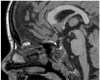

Results: A 6-year-old patient was admitted for right otomastoiditis and thrombosis of the sigmoid and transverse sinuses, as well as the proximal portion of the internal jugular vein. Radiological examinations revealed a left orbital mass (22 × 14 mm) compatible with asymptomatic orbital meningocele (MC) herniated from the superior orbital fissure (SOF). The child underwent a right mastoidectomy. After the development of symptoms and signs of intracranial hypertension (ICH), endovascular thrombectomy and transverse sinus stenting were performed, with improvement of the clinical conditions and reduction of the orbital MC. The systematic literature review encompassed 29 publications on 43 patients with spontaneous orbital MC. In the majority of cases, surgery was the preferred treatment.